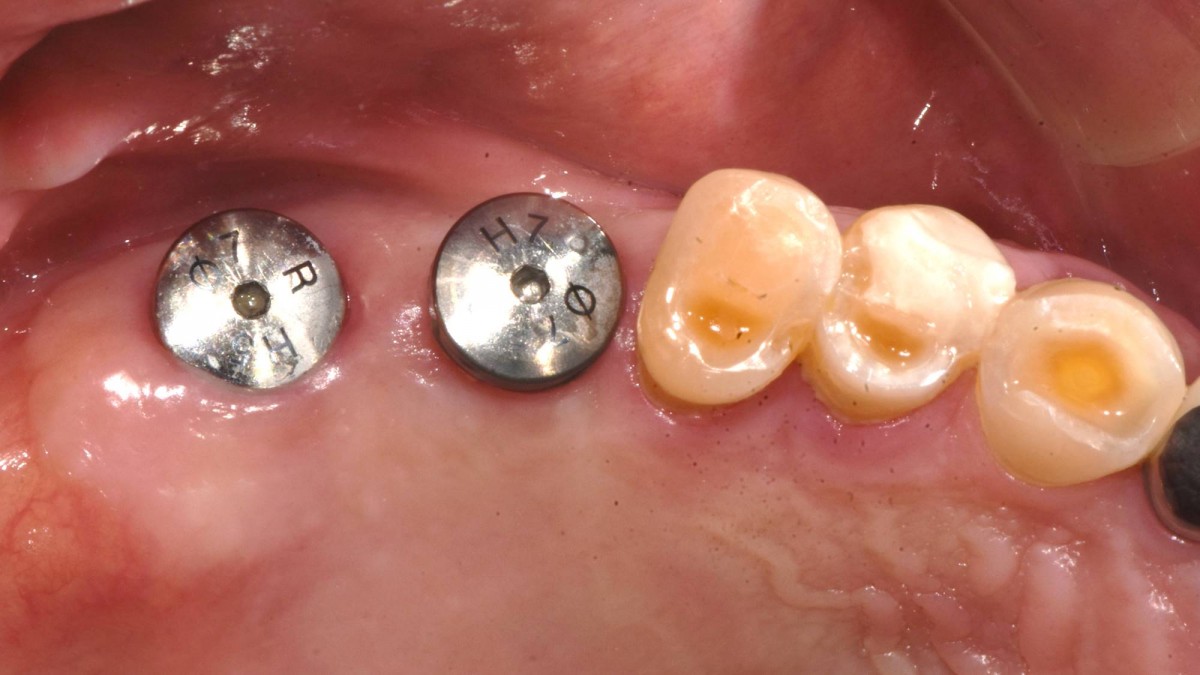

Socket Lift and Implant Placement in the right maxilla.

<GCacg> A 56-year-old male patient complained of pain in the right upper and lower jaws. And he wanted the upper first molar to be pulled out first.